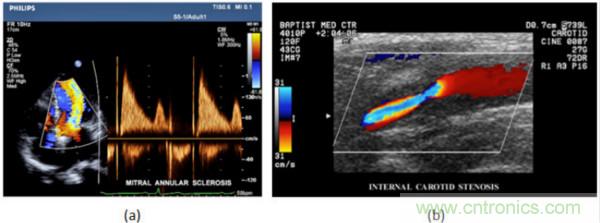

在CW和PW多普勒模式中,流信息是從一個(gè)聚焦聲束中獲得的,類(lèi)似于A模式成像。在20世紀(jì)80年代,研究人員基于彩色多普勒技術(shù)完成了血流分布的二維信息可視化。彩色多普勒處理也是基于B模式/PW模式信號(hào)路徑。從感興趣區(qū)域收集多幀RF數(shù)據(jù)。由于感興趣區(qū)域中的血液流動(dòng)導(dǎo)致圖像幀之間存在數(shù)據(jù)差異。相域中的自相關(guān)和時(shí)域中的互相關(guān)兩種算法可從RF數(shù)據(jù)中提取數(shù)據(jù)方差(即血流速度和方向信息):。根據(jù)預(yù)定義的顏色漸變條相應(yīng)地映射包括速度和方向的血流信息。通常,藍(lán)色和紅色代碼分別識(shí)別朝向和遠(yuǎn)離換能器移動(dòng)的血流。當(dāng)流速增加時(shí)使用更亮的顏色,反之亦然。顏色映射的2D分布始終疊加在B模式圖像上,以實(shí)時(shí)同時(shí)顯示個(gè)體解剖結(jié)構(gòu)和血流。它對(duì)于診斷心血管疾病,如血管閉塞和心臟瓣膜反流,極其有用。典型的彩色多普勒?qǐng)D像如下圖所示,(b)顯示頸動(dòng)脈狹窄引起的血流流速變化。

圖7.彩色多普勒成像:(a)以彩色多普勒和CW模式獲得的圖像(由Philips提供); (b)顯示頸動(dòng)脈狹窄的彩色多普勒(由GE提供)